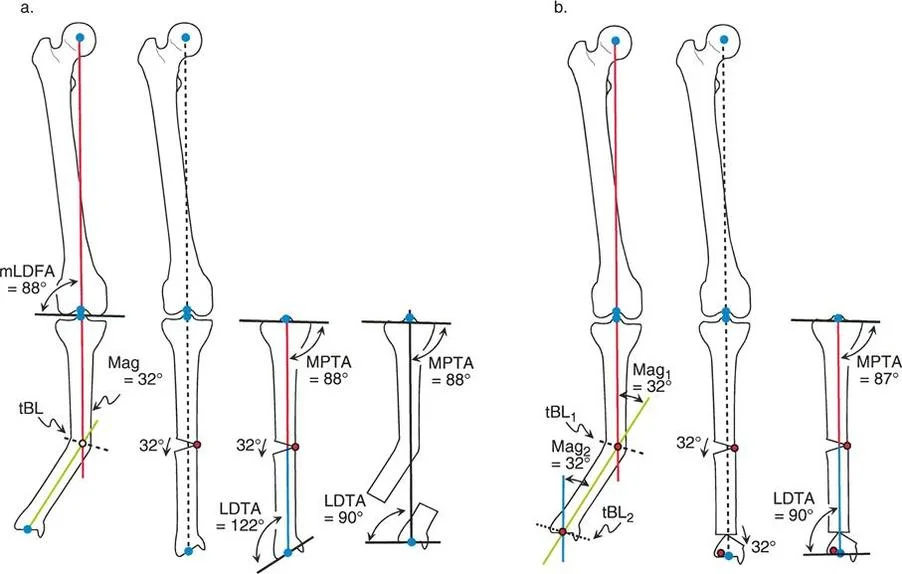

زوايا اتجاه المفاصل

إن استعادة المحور الميكانيكي إلى وضعه الطبيعي هو جزء من المعركة فقط. فالساق المستقيمة التي تحتوي على مفاصل "معوجة" ستتدهور بسرعة. تقيس زوايا اتجاه المفاصل العلاقة بين المحور الميكانيكي (أو التشريحي) للعظم وخط المفصل الخاص به. هذه الزوايا ضرورية لضمان توزيع الحمل بالتساوي عبر سطح المفصل:

- الزاوية الفخذية الأنسية البعيدة (mLDFA): تقيس اتجاه مفصل الركبة بالنسبة لعظم الفخذ. يتراوح المعدل الطبيعي عادةً بين 85 درجة و 90 درجة (بمتوسط 88 درجة).

- الزاوية الظنبوبية القريبة الأنسية (MPTA): تقيس اتجاه مفصل الركبة بالنسبة لعظم الساق (الظنبوب). يتراوح المعدل الطبيعي عادةً بين 85 درجة و 90 درجة (بمتوسط 87 درجة).

- الزاوية الظنبوبية البعيدة الوحشية (LDTA): تقيس اتجاه مفصل الكاحل بالنسبة لعظم الساق (الظنبوب). يتراوح المعدل الطبيعي عادةً بين 86 درجة و 92 درجة (بمتوسط 89 أو 90 درجة).

منهجية مركز دوران الزاوية (CORA)

مركز دوران الزاوية (CORA) هو النقطة التي تتقاطع فيها المحاور الميكانيكية القريبة والبعيدة للعظم. ببساطة، هو النقطة التي يحدث فيها الانحناء في العظم.

* المحور الميكانيكي القريب (PMA): خط يمتد من مركز المفصل القريب، موجهًا بزاوية المفصل الطبيعية.

* المحور الميكانيكي البعيد (DMA): خط يمتد من مركز المفصل البعيد، موجهًا بزاوية المفصل الطبيعية.

يحدد تقاطع هذين الخطين حجم وموقع التشوه. ولكن ماذا يحدث عندما يحتوي العظم على أكثر من تشوه واحد؟ هذا يقودنا إلى معضلة التشوه متعدد المستويات.